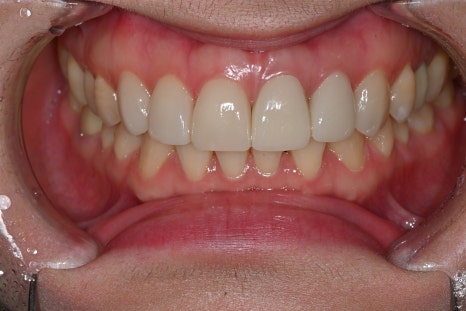

초진 시 파노라마와 구강 사진을 촬영해

전체 치아 상태를 확인했고,

특히 앞니 라인의 색·투명도·대칭이

전체적인 인상을 좌우하고 있어

라미네이트와 전치부 크라운을 조합한

설계가 가장 적합하다고 판단했습니다.

크라운 재제작을 동반한 오브제로시술

이 케이스에서는 총 6개 영역을 디자인했습니다.

오브제로 퓨어는 자연광에서의 재현력이 좋고,

지르코니아 크라운은 강도와 색 안정성이 높아

앞니 기능 회복과 심미를 함께 잡을 수 있는 조합입니다.